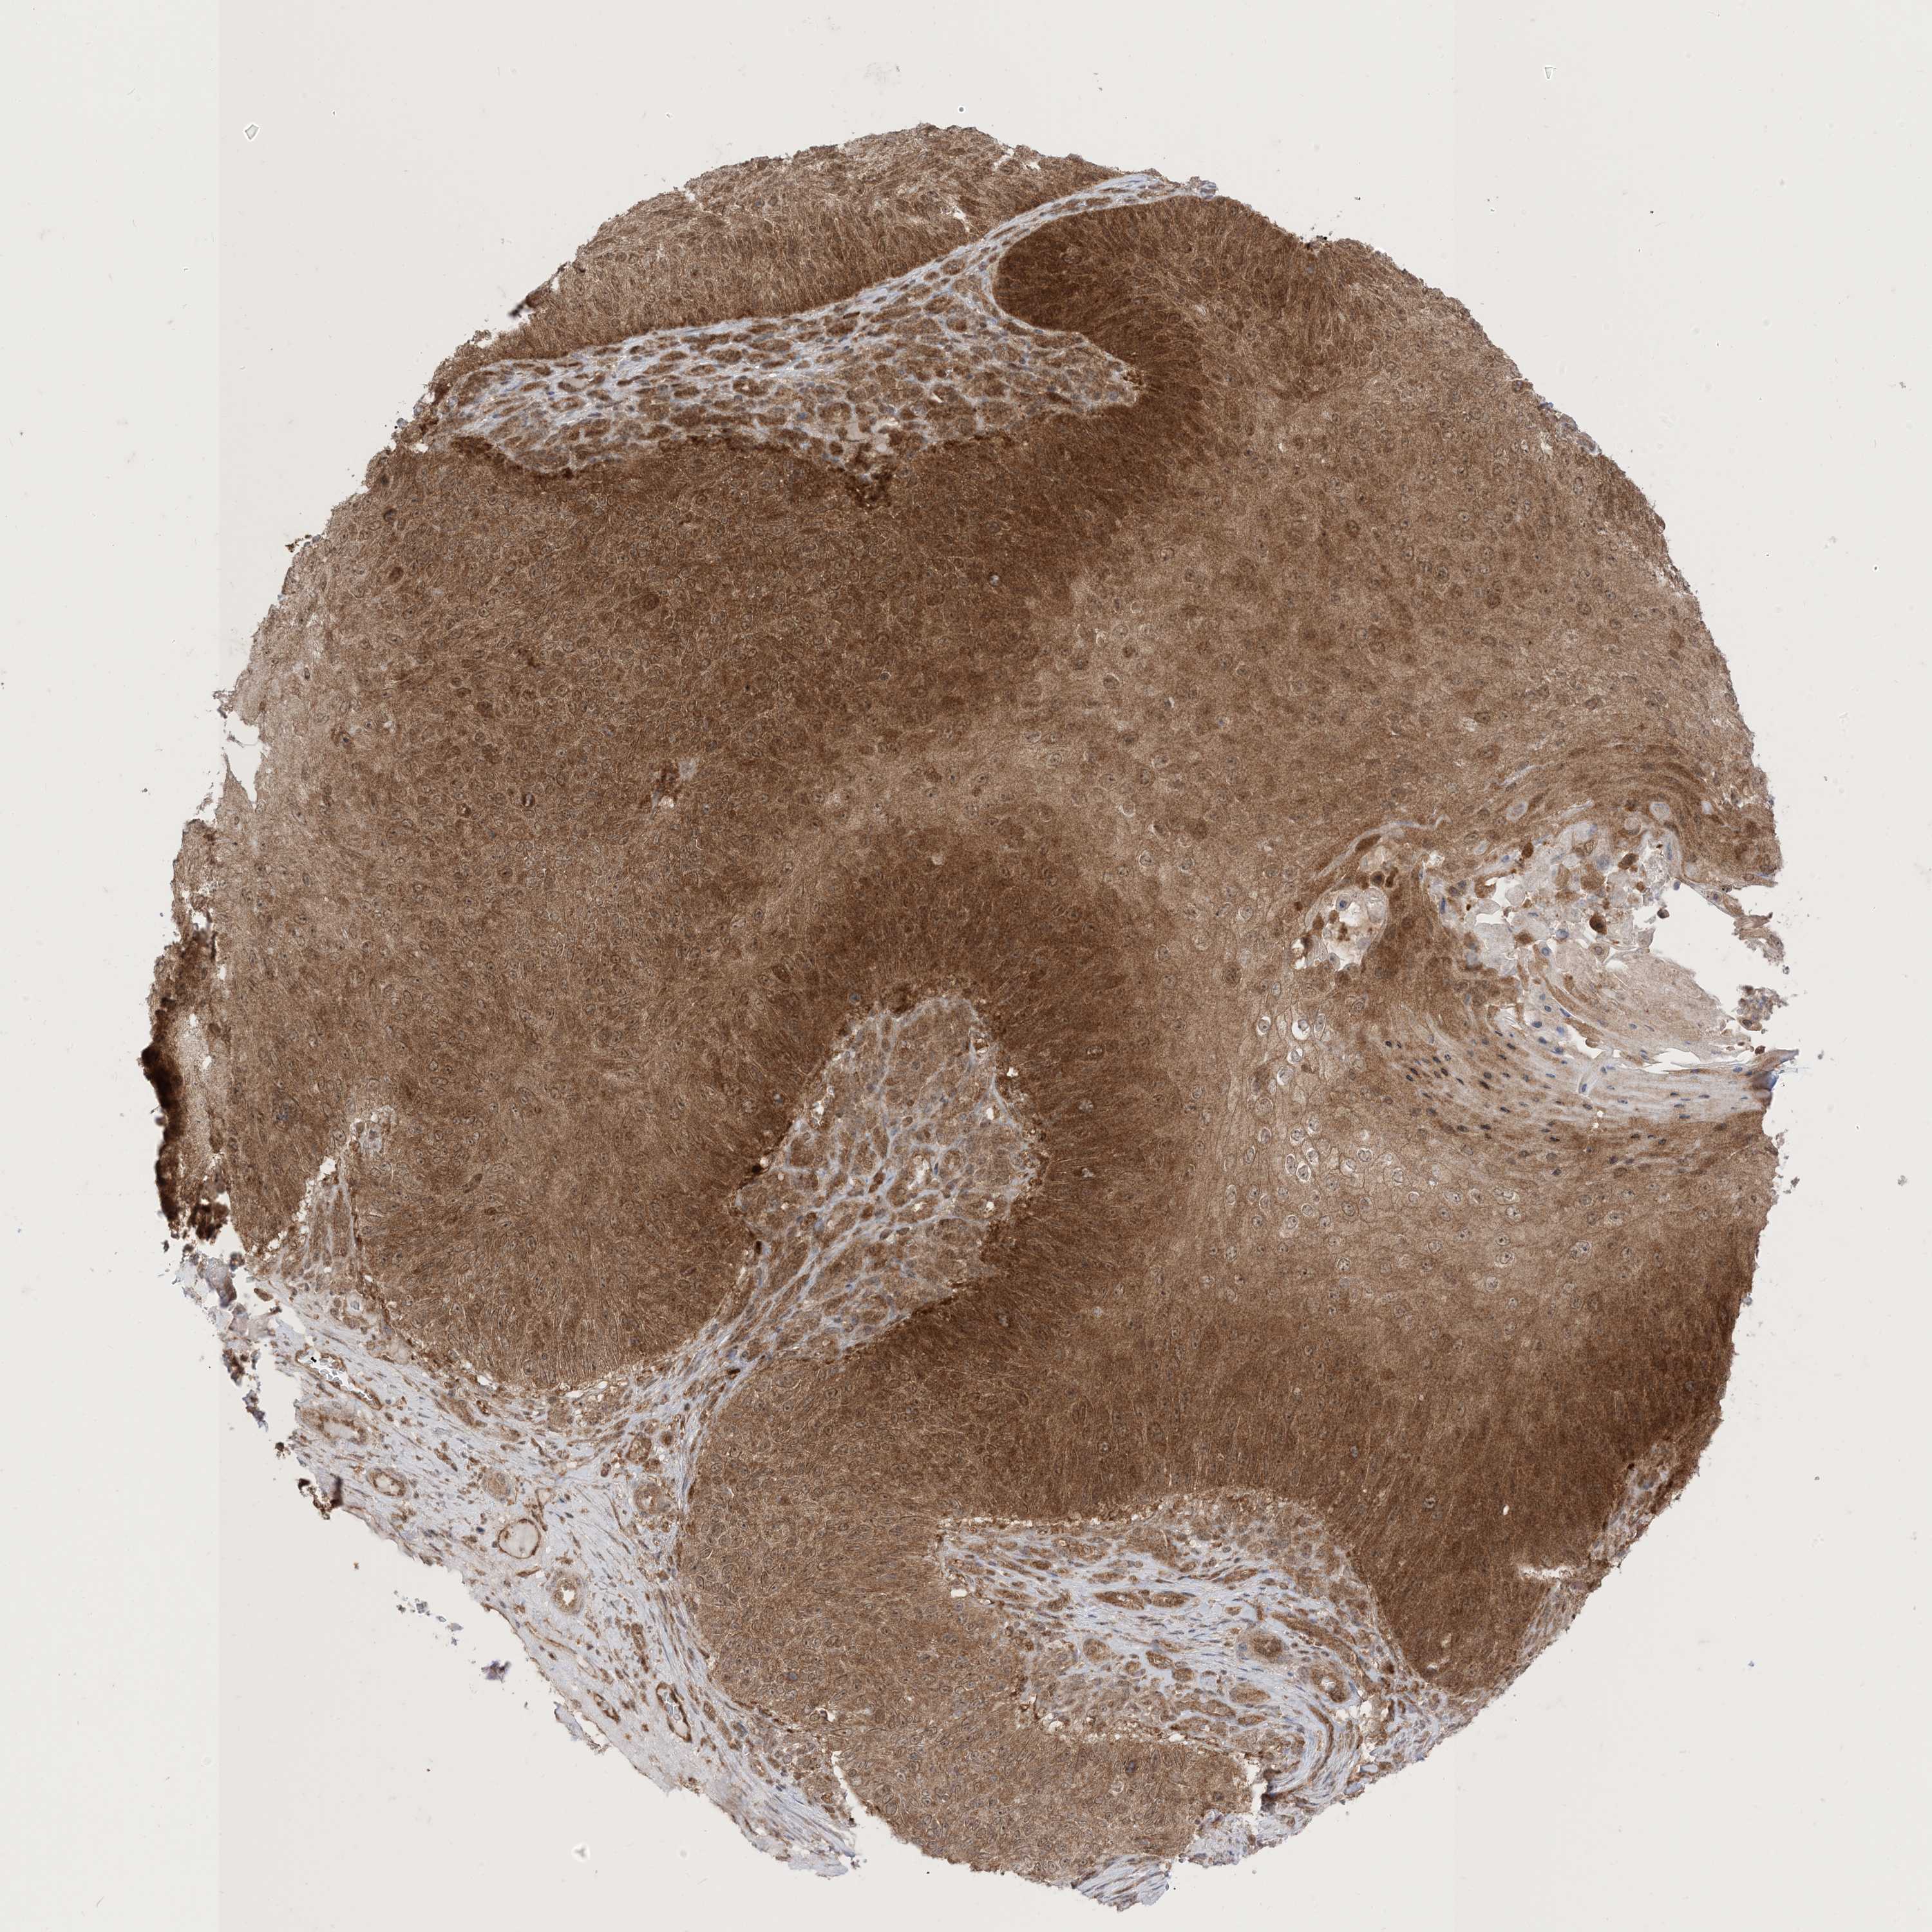

SKIN CANCER - Protein expressioni

A mouse-over function shows sample information and annotation data. Click on an image to view it in a full screen mode. Samples can be filtered based on level of antibody staining by selecting one or several of the following categories: high, medium, low and not detected. The assay and annotation is described here.

Antibody stainingi

Antibody staining in the annotated cell types in the current human tissue is reported as not detected, low, medium, or high, based on conventional immunohistochemistry profiling in selected tissues. This score is based on the combination of the staining intensity and fraction of stained cells.

Each image is clickable and will lead to virtual microscopy that enables deeper exploration of all samples and also displays staining intensity scores, fraction scores and subcellular localization as well as patient and tissue information for each sample.

HPA005695

Staining

High

Medium

Low

Not detected

Intensity

Strong

Moderate

Weak

Negative

Quantity

>75%

75%-25%

<25%

None

Location

Nuclear

Cytoplasmic/membranous

Cytoplasmic/membranous,nuclear

Squamous cell carcinoma, NOS